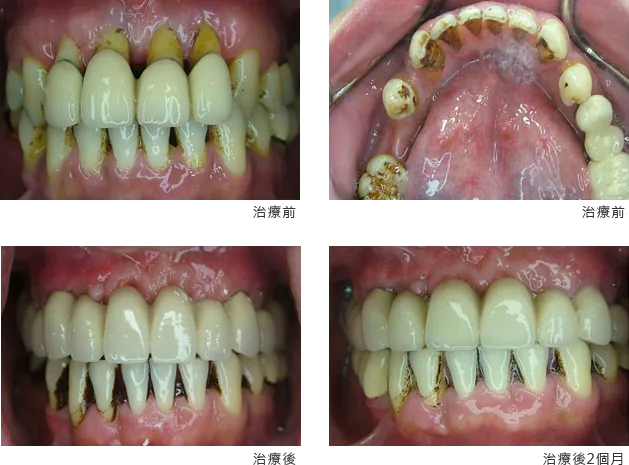

[ 王先生植牙案例 ]